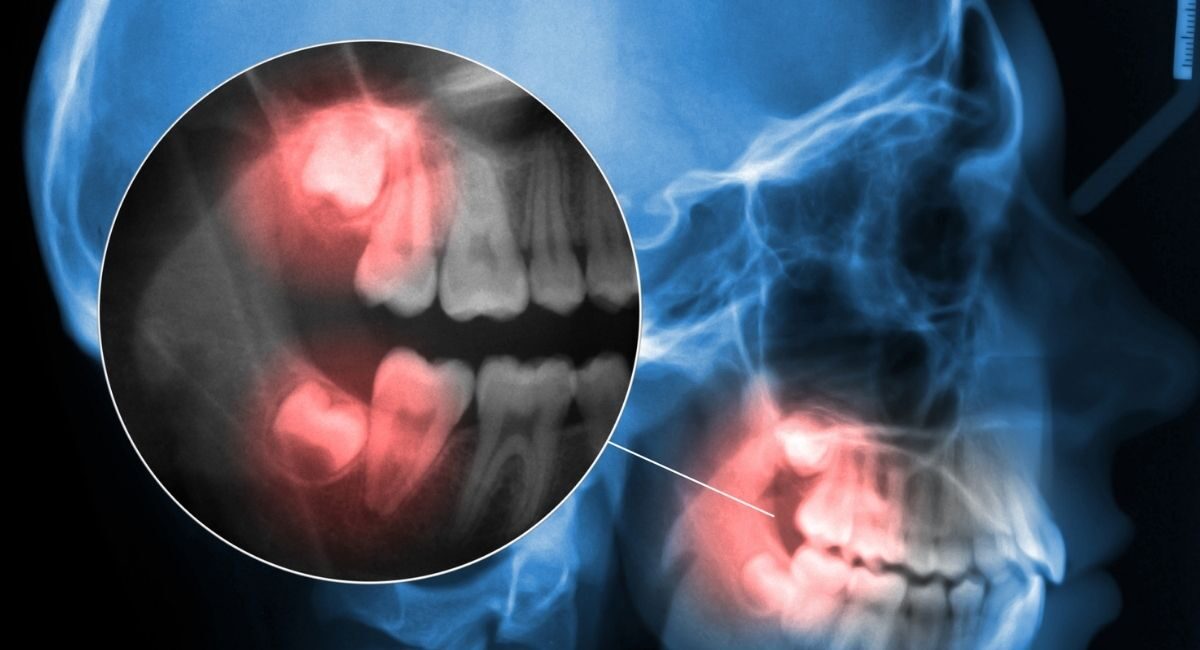

When wisdom teeth do not emerge correctly, they can become impacted or partially erupted, leading to a variety of dental issues.

- Impacted wisdom teeth

When a tooth becomes trapped beneath the gum or bone, it may grow sideways or push against neighbouring teeth. - Pain or discomfort

In many cases, wisdom teeth removal is recommended as a preventive measure, especially when x-rays show potential complications developing.

Wisdom teeth removal is a common and routine dental procedure. Before treatment, your dentist will perform a thorough examination and take dental x-rays to understand the position of the teeth and plan the procedure safely.